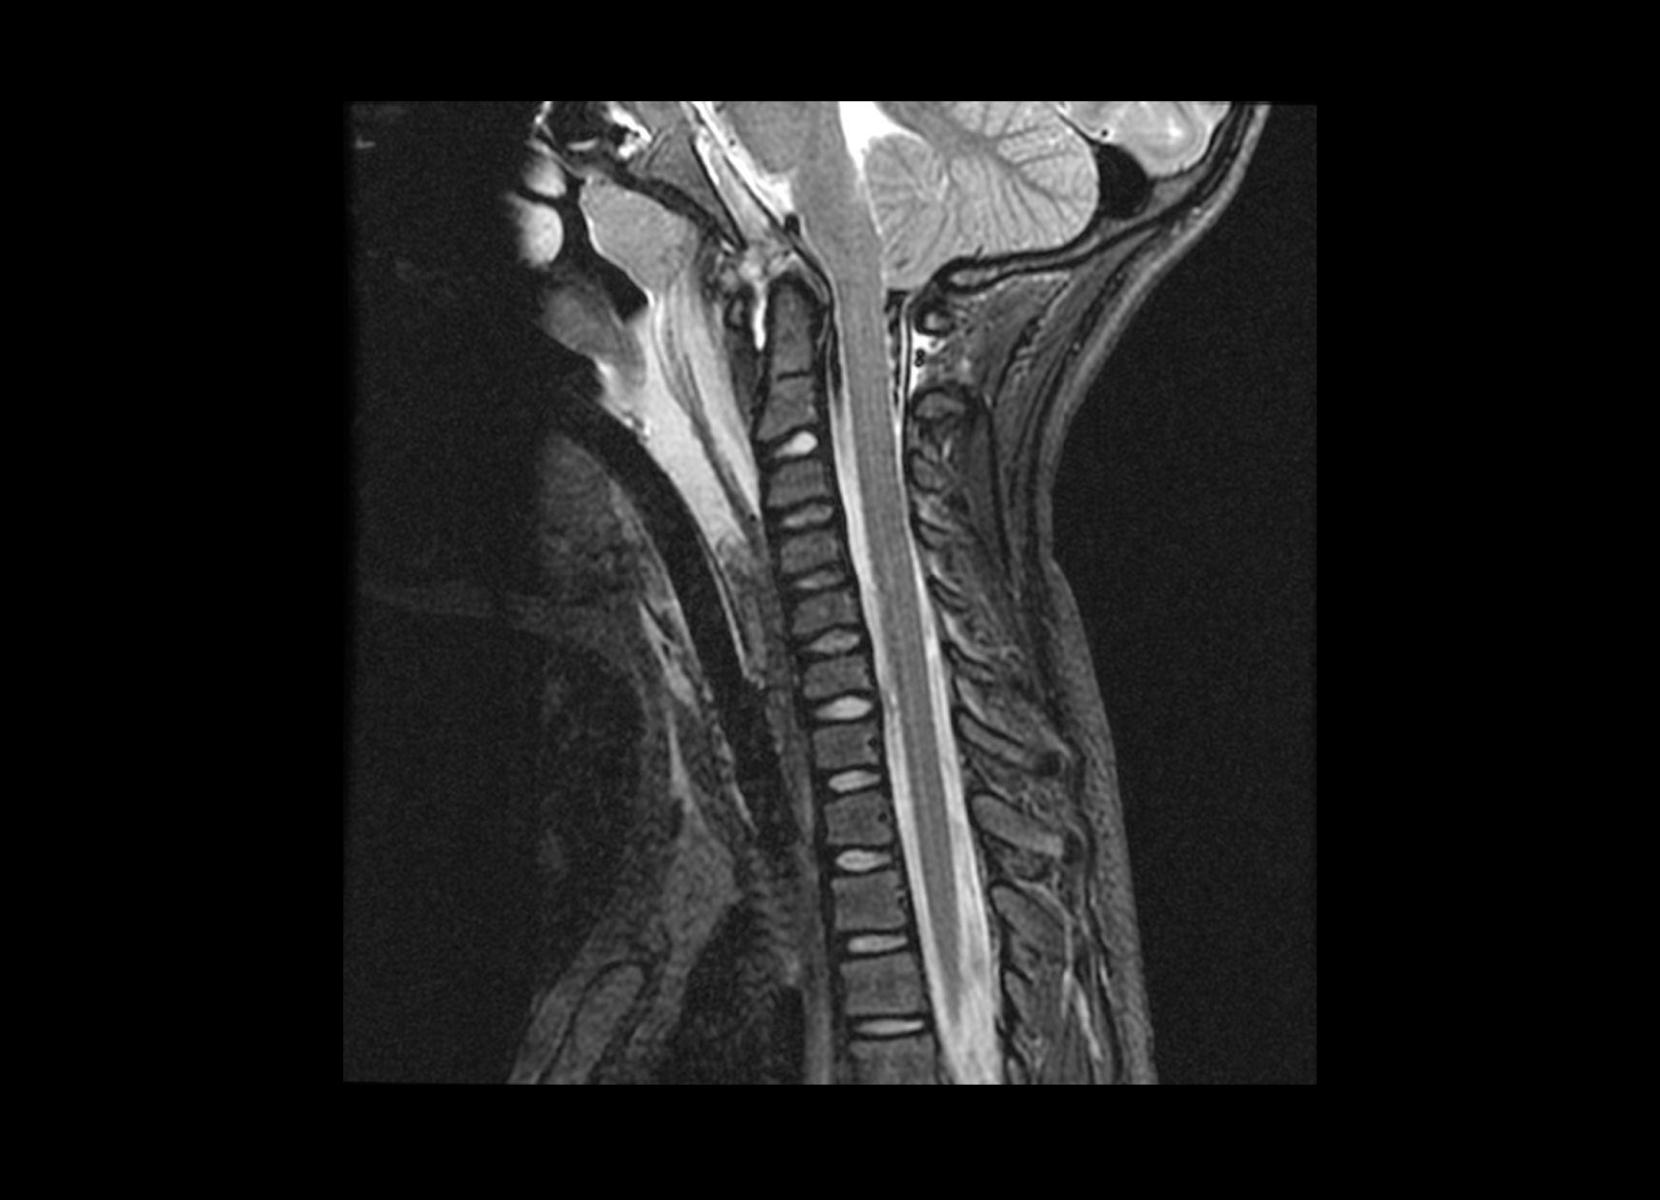

Normal

GE 3T

C-spine

Conventional

STIR

SubtleSYNTH™

(Synthesized STIR)™